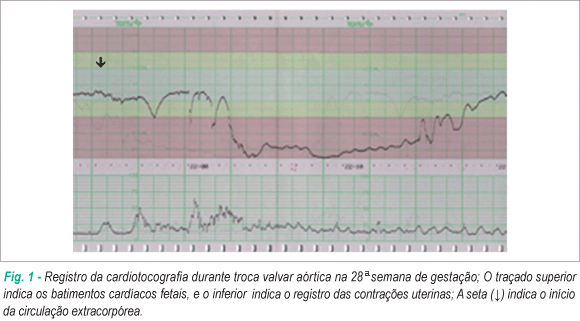

Diagnóstico: A Cardiotocografia Intraparto

A principal ferramenta para o diagnóstico do sofrimento agudo é a cardiotocografia (CTG). A sua interpretação baseia-se na análise de múltiplos parâmetros:

- Linha de Base: Frequência cardíaca fetal (FCF) média em um traçado de 10 minutos. O normal situa-se entre 110 e 160 batimentos por minuto (bpm). Valores acima de 160 bpm definem taquicardia, e abaixo de 110 bpm, bradicardia.

- Variabilidade: Oscilações da FCF em torno da linha de base. A variabilidade moderada (6 a 25 bpm) é considerada normal e um forte indicador de um sistema nervoso autônomo íntegro. A variabilidade ausente é um sinal alarmante.

- Acelerações Transitórias: Aumentos temporários da FCF, considerados o melhor marcador de bem-estar fetal. Para fetos com idade gestacional (IG) > 32 semanas, define-se como um aumento de 15 bpm por 15 segundos.

- Desacelerações: Quedas transitórias da FCF, classificadas em:

- Tipo I (Precoce ou DIP I): Queda gradual e simétrica da FCF, cujo ponto mais baixo (nadir) coincide com o pico da contração uterina. É causada pela compressão do polo cefálico (reflexo vagal) e não se associa à hipóxia.

- Tipo II (Tardia ou DIP II): Queda gradual com nadir posterior ao pico da contração. Este padrão indica insuficiência uteroplacentária e hipóxia fetal.

- Tipo III (Variável ou Umbilical): Queda abrupta e de morfologia variável, causada pela compressão do cordão umbilical. Podem não estar associadas a sofrimento fetal, mas critérios como duração superior a 60 segundos, queda abaixo de 70 bpm e retorno lento à linha de base indicam mau prognóstico.

- Padrão Sinusoidal: Um padrão ondulatório, rítmico e regular, que é um sinal ominoso de anemia fetal grave e hipoxemia, com alto risco de óbito intraútero.